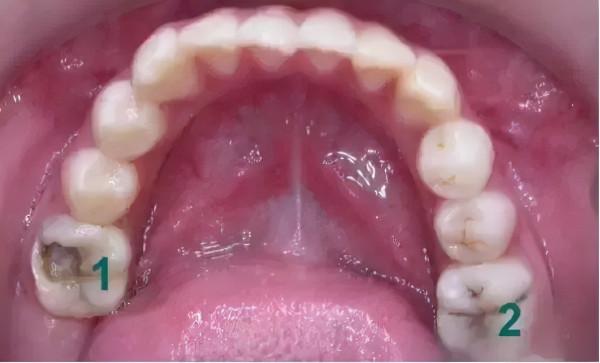

最早因為疏忽大意,一檢查小小常爛掉了4顆牙齒,治療的時候在診室裡哇哇大哭了整整一個小時。

有一顆牙爛得特別狠,明明牙面上只是一個牙籤大小的黑洞,可是當醫生清理牙洞時,沒想到大半個牙是空的了,細菌已經把結實的牙質腐爛至牙神經,不得已就做了根管治療。嗞嗞的鑽頭聲,感覺都鑽進了我的腦殼,心疼又頭疼!!

這顆牙齒在萌出時多數沒有疼痛或不適的感覺,悄悄地萌出長好,很多父母不知道這一點,光盯著前面的牙怎麼還沒掉長新牙,以為孩子一口牙全部都要換,即使看到後面牙爛掉,心想壞了也沒事(以為是乳牙)反正還要換,而沒能及時給予這顆牙足夠的關注和保護,導致它早早就出了問題,這樣痛心的案例真的是太多了。